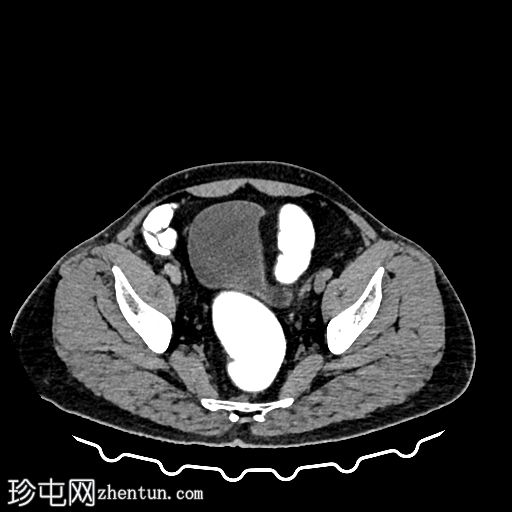

乙状结肠旁可见两处小的脂肪衰减病灶。较小的病灶呈周边环状强化,伴有轻度邻近脂肪条索状改变 → 急性大网膜垂炎。

较大的病灶呈薄环状强化,周围无炎症 → 消退期/慢

性病

变。未见肠壁增厚,未见肠腔相通,无游离液体或积液。

大网膜垂炎是指由于扭转或静脉血栓形成引起的大网膜垂缺血性炎症,最常见于乙状结肠旁。 CT

影像

具有特征性,有助于避免不必要的抗生素或手术。